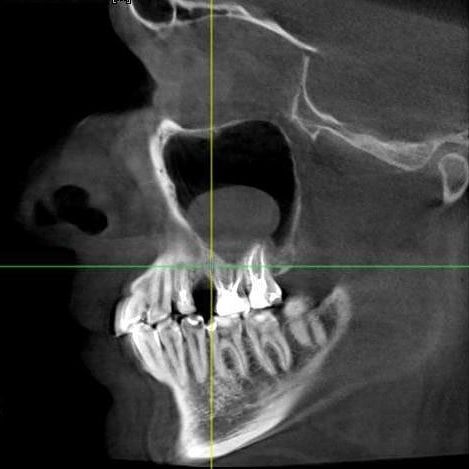

Тут то все и выяснилось. Оказалось, что причиной вечного насморка была не аллергия, а именно этот зуб (точнее его полуразрушенная пломба). Наши дальние зубы связаны с пазухами носа. И при отсутствии заболевания, они (пазухи) стерильны. А вот если в них попадает какой-либо возбудитель (бактерии, инородные вещества), то в пазухах обнаруживается слизь, которую мы называем соплями, и начинает течь из носа. На этом примере через разрушенную часть зуба проникала всякая дрянь из ротовой полости, что приводило к раздражению гайморовой пазухи, которая в результате самоочищения выдавала постоянный ринит! Вот так загадка!